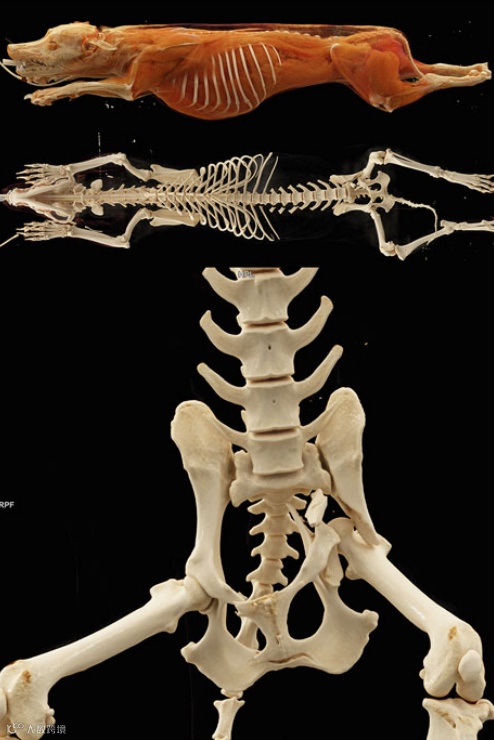

就...挺像人的

太长扫不完的可能得折叠一下

狗的轴位CT图

你认得出哪几个器官呢?